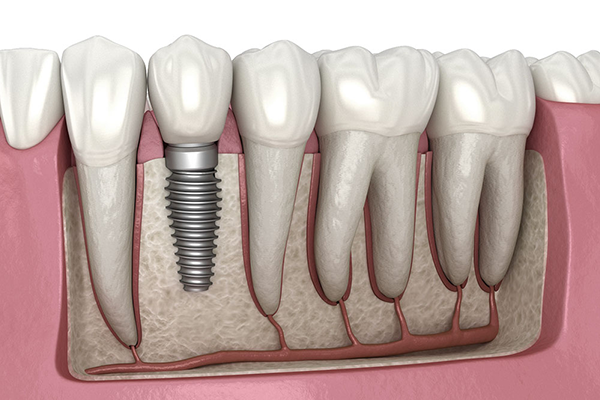

With over 27 years of clinical excellence in Thane, Dr Tamhane's DenTrio Dental Implants & Laser Clinic has been transforming smiles and changing lives. Our multi-specialty team combines decades of expertise with cutting-edge dental technology to deliver exceptional, patient-first care.